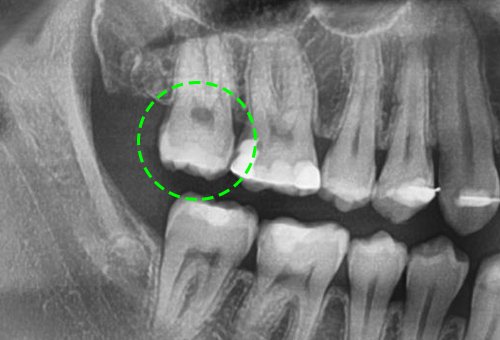

• 매복된 사랑니

아직 자라지 않았거나, 머리 부분만 자란 사랑니는 간혹 치아를 둘러싸고 있는 치아주머니에 물이 차

염증반응을 일으키기 쉽기 때문에 눈에 보이지 않더라도 발치하는 것이 좋습니다.